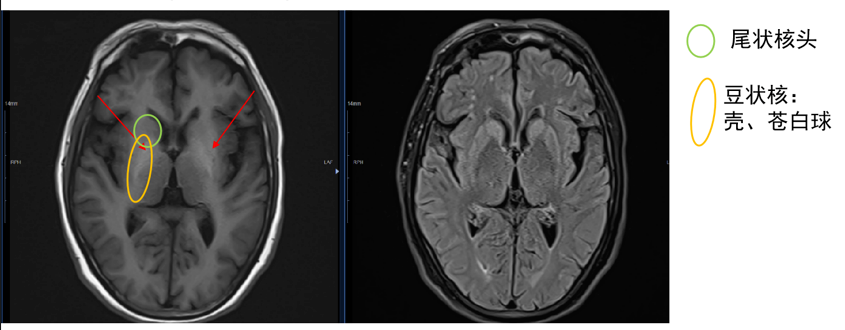

(3)颅脑MR:T1WI上双侧苍白球出现对称性高信号,考虑锰等神经毒性物质积累所致(图2)。

图2. 颅脑MR平扫的T1WI(左)和T2-FLAIR(右)序列。T1WI上双侧苍白球出现对称性高信号,考虑锰等神经毒性物质积累所致。T2-FLAIR上双侧基底节未见异常信号,原双侧尾状核和壳核高信号消失

(源自讲者幻灯)

诊疗经过:结合患者锥体外系症状,血氨升高和颅脑MR新发改变,考虑诊断为慢性HE并发帕金森样综合征,又称为AHCD。在补充甲状腺素、保肝、降氨等治疗基础上加用盐酸普拉克索缓释片(0.125 mg qd)治疗锥体外系症状。患者能独立行走后出院。